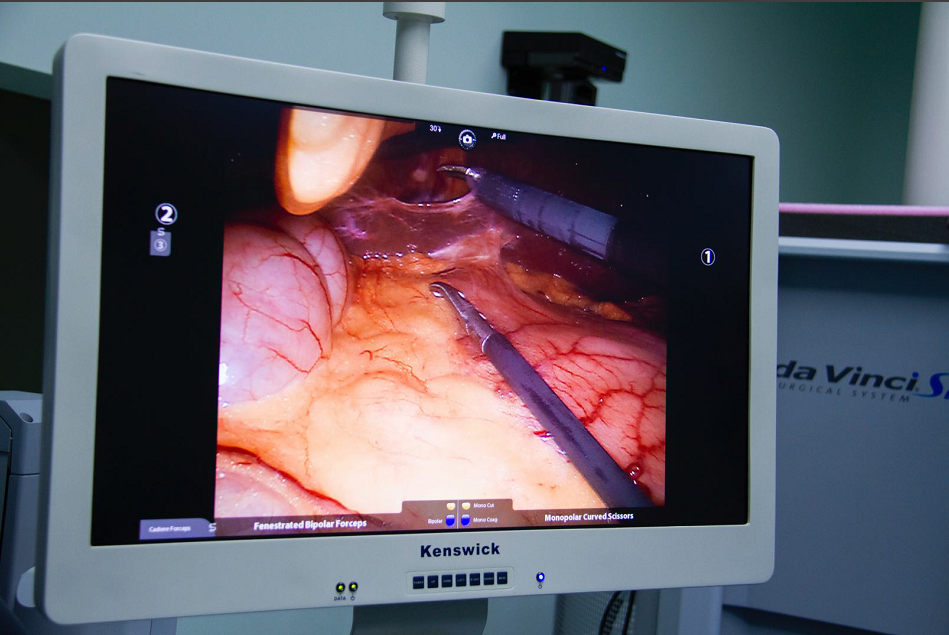

达芬奇手术机器人的全称是内窥镜手术器械控制系统(英文名da Vnici S),它与腹腔镜系统相结合,主刀外科医师在远离手术台的操作控制台,用手遥控着装配在手术台上的4个机械臂,控制连接在机械臂上的腹腔镜和手术器械的动作和运转,完成各类手术。可以说达芬奇手术机器人的出现,将外科医师从手术台上解放了出来。

1、机器人的摄像系统为外科医师提供了更清晰和逼真的三维视野,机器人的“眼睛”高清立体,手术视野放大10倍,细小的组织也难逃火眼金睛;

这些优势改变了传统腹腔镜视野失真、操作不灵活、手术难度大的缺陷,使外科医师如虎添翼。正因为如此,达芬奇手术机器人在完成泌尿外科的前列腺癌根治术、膀胱癌根治术、肾部分切除术等高难度手术时也可以大显身手。通过更清晰的视野、精细的解剖、精准的操作缩短了手术时间、减少了出血量和并发症,使患者得到更快的术后恢复和更好的疗效。

光学放大10倍的高清晰立体图像